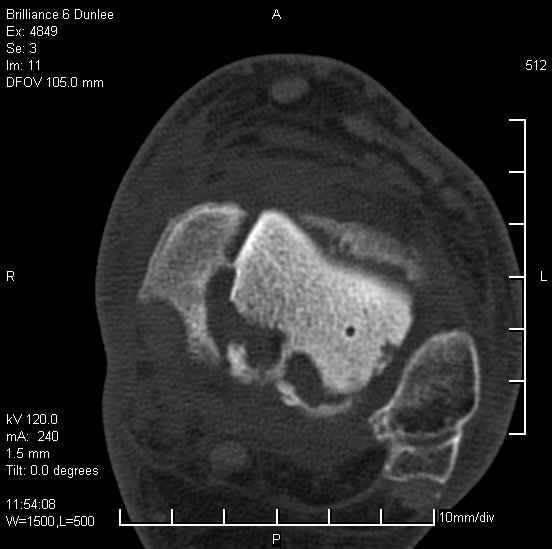

Асептический некроз таранной кости.

На лечении находится пациент 35 лет. Травма в сентябре 2008 г.- открытый вывих таранной кости

В день травмы ПХО, вправление вывиха, трансартикулярная фиксация. Рана зажила первично. С января нагрузка на конечность. С конца апреля- болевой синдром. На рентгенограммах и КТ признаки ас. некроза таранной кости, артроз подтаранного и голеностопного суставов.

У больного тотальный ас. некрох блока таранной кости, заинтересованы голеностопный и подтараный суставы. Эндопротезирование маловероятно на некротизированную кость. Изолированный подтаранный артродез таран не спасет.При артродезе всю некротизированную кость придется убрать.А далее замещение либо за счет большеберцовой кости, или удлинение на регенерате.